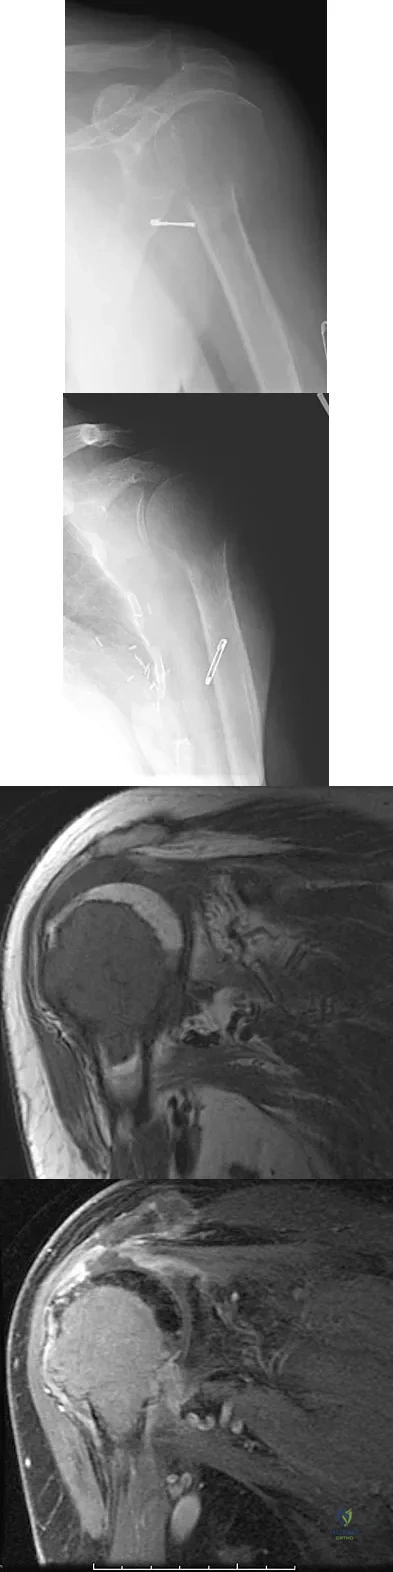

Examination of the shoulder seen in Figure 52 shows atrophy and tenderness of the infraspinous fossa and profound weakness in external rotation. The supraspinous fossa shows normal muscle bulk. What is the most likely cause of this condition?

A 72-year-old woman who is right hand-dominant has severe pain in the right shoulder that has failed to respond to nonsurgical management. She reports night pain and significant disability. Examination reveals 30 degrees of active forward elevation. An AP radiograph is shown in Figure 27. Which of the following treatment options will provide the best functional improvement?

Figures 36a and 36b show the MRI scans of a patient who has shoulder weakness. What is the most likely diagnosis?

A 79-year-old woman with polyarticular rheumatoid arthritis has had progressively increasing right shoulder pain for the past year, and nonsurgical management has failed to provide relief. Her neurologic examination is entirely normal, but she is unable to elevate her arm against gravity. An AP radiograph is shown in Figure 13. Treatment should consist of

A patient has right shoulder pain. Figure 1a shows a gadolinium-enhanced transverse MRI scan at the level of the coracoid. Figure 1b shows an arthroscopic view of the anterior structures from a posterior portal. These images reveal which of the following findings?

Figures 47a through 47f show the AP radiograph, bone scan, CT scan, MRI scan, and biopsy specimens of a 30-year-old woman who has had vague left shoulder pain for 1 year. Management should consist of